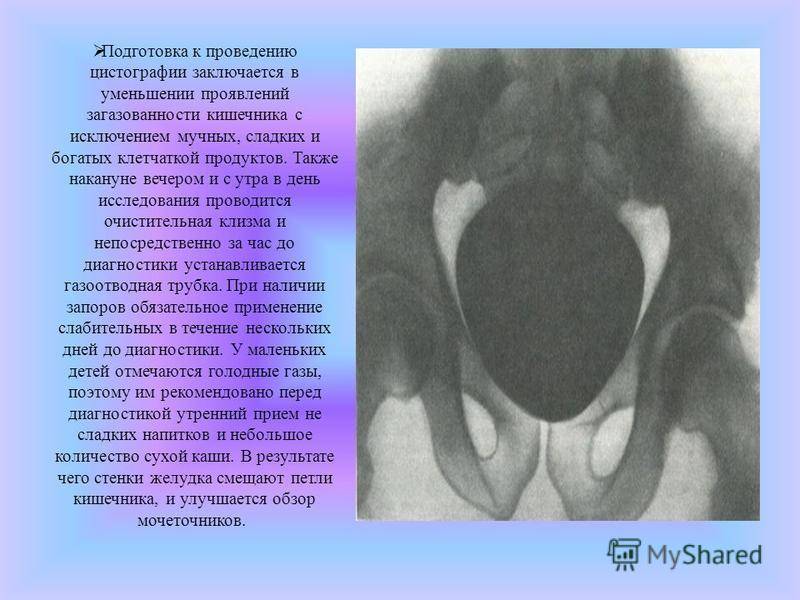

Медицинские изображения и примеры эксреторной цистографии